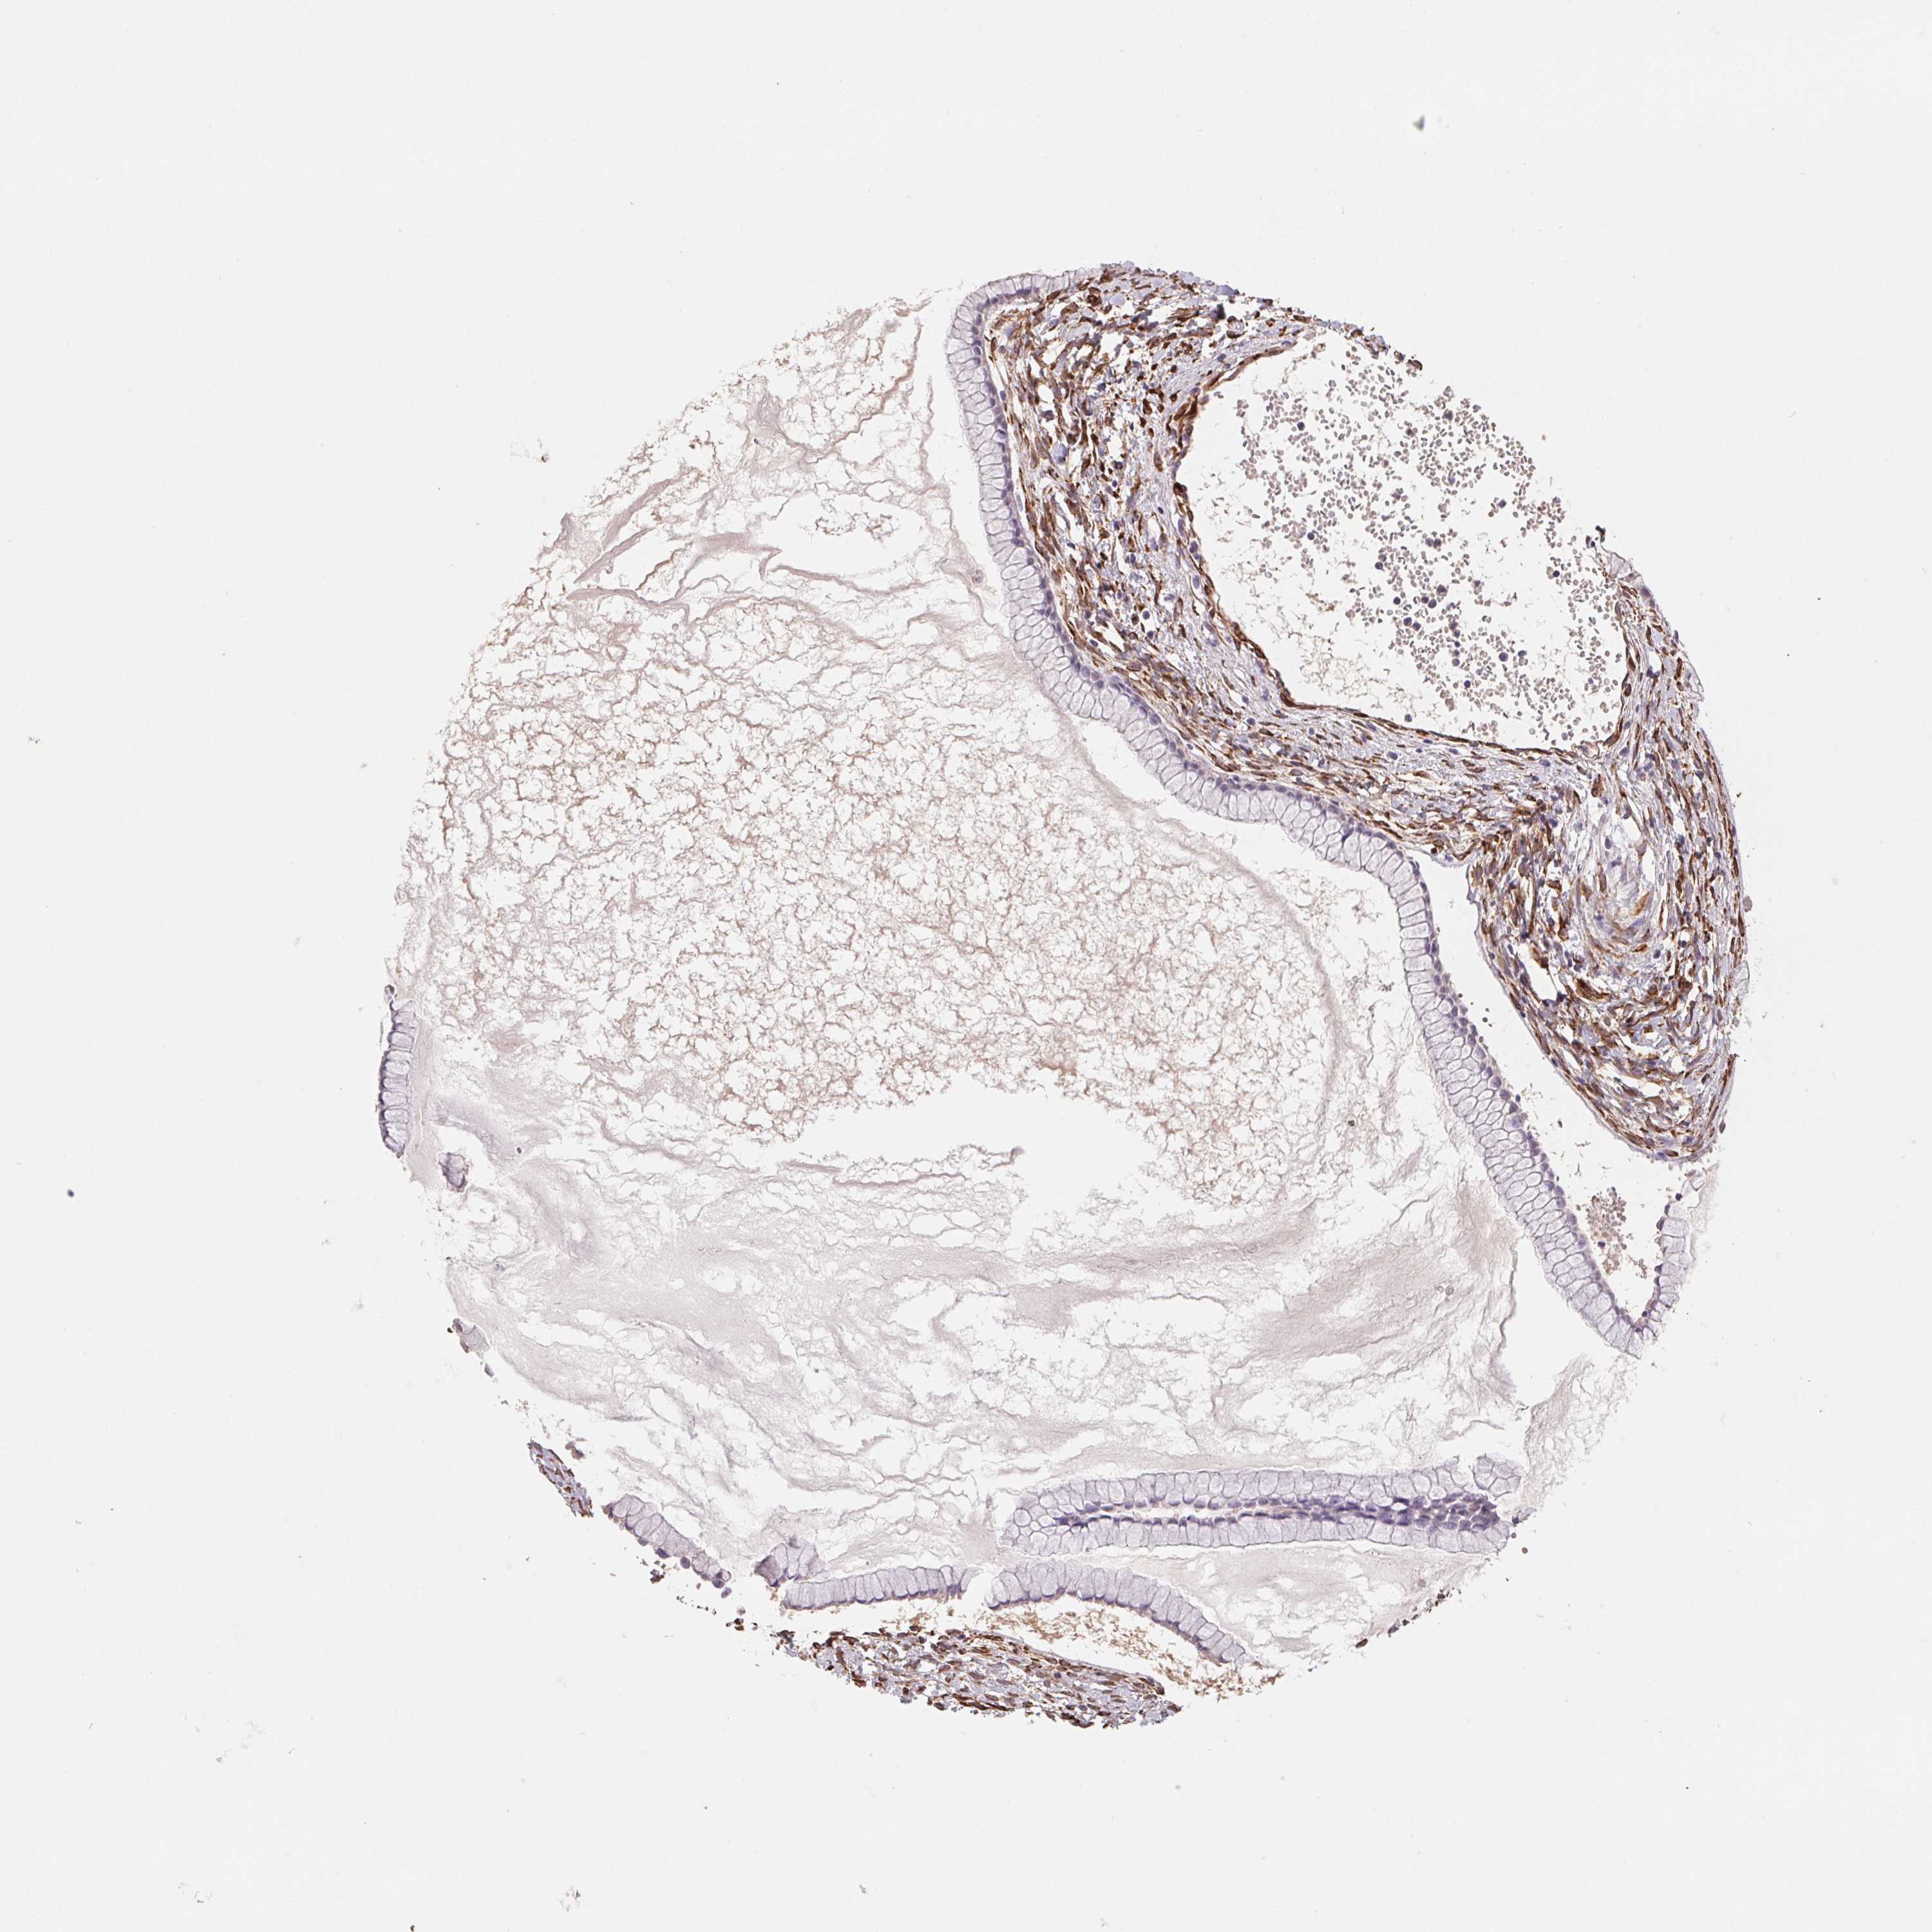

OVARIAN CANCER - Protein expressioni

A mouse-over function shows sample information and annotation data. Click on an image to view it in a full screen mode. Samples can be filtered based on level of antibody staining by selecting one or several of the following categories: high, medium, low and not detected. The assay and annotation is described here.

Note that samples used for immunohistochemistry by the Human Protein Atlas do not correspond to samples in the TCGA dataset.

Antibody stainingi

Antibody staining in the annotated cell types in the current human tissue is reported as not detected, low, medium, or high, based on conventional immunohistochemistry profiling in selected tissues. This score is based on the combination of the staining intensity and fraction of stained cells.

Each image is clickable and will lead to virtual microscopy that enables deeper exploration of all samples and also displays staining intensity scores, fraction scores and subcellular localization as well as patient and tissue information for each sample.

Antibody HPA051171

Antibody HPA057021

Cystadenocarcinoma, serous, NOS

Carcinoma, NOS

Cystadenocarcinoma, mucinous, NOS

Carcinoma, endometroid